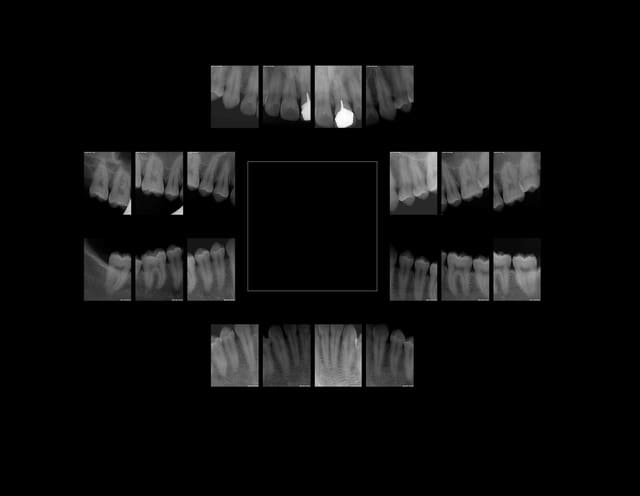

Voilà tu as tout pigé. Cas d'école : MR X seule la 21 (que je n'aurais pas du faire car aucun signe clinique) , est valable selon le CDC.

Mr x  x9dahq - Eugenol